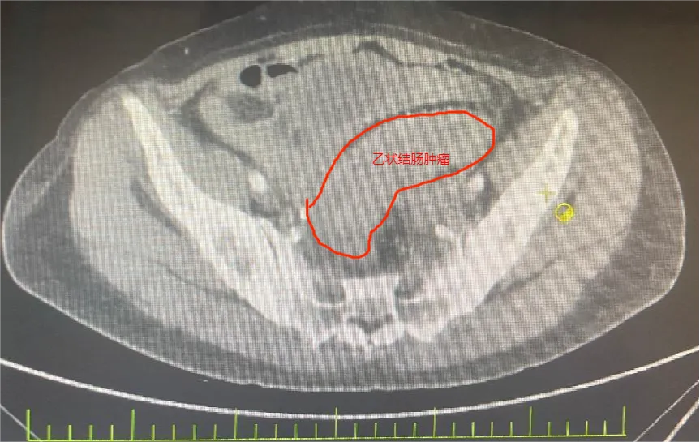

她被确诊为乙状结肠癌,肿瘤已“疯狂”侵犯膀胱、子宫、输尿管等多个盆腔脏器,还伴随不全性肠梗阻。2个月前在外院住院治疗,因手术风险大,外院仅为她做了横结肠造口术缓解梗阻,可术后不幸出现结肠膀胱瘘——小便中混着大便的症状让她痛苦不堪,叠加尿路感染、肿瘤引发的消化道出血,以及尿路梗阻导致的肾功能不全,多重并发症叠加,生活质量跌至谷底。

先是完整切除受肿瘤侵犯的直肠与乙状结肠原发灶,紧接着剥离与肿瘤紧密粘连的子宫及双侧附件并完整移除,随后小心翼翼分离膀胱与周围组织,将受侵膀胱全部切除——前三项切除手术已耗极大精力,团队仍需在腹腔镜下用回肠精心构建新的膀胱通路,确保患者术后排尿功能正常。